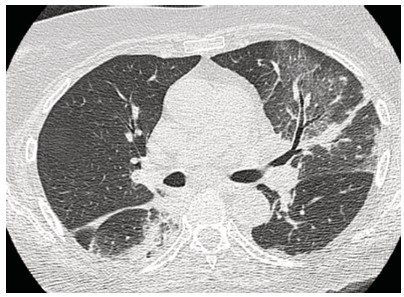

Mujer de 73 años procedente de Australia con antecedentes de hipertensión arterial, depresión, tiroiditis de Hashimoto e hipotiroidismo secundario. En las últimas semanas, como parte de su recorrido por Sudamérica, visitó Chile, Brasil, Argentina y Perú. En este último y durante su estancia en Machu Picchu, debuta con un cuadro clínico caracterizado por astenia, disnea de moderados esfuerzos, tos seca y cefalea opresiva holocraneana, tratada con medicación no especificada con mejoría parcial. Sin embargo, pocos días después y tras su llegada a Ecuador los síntomas se agudizan con aumento de la frecuencia e intensidad de la tos, así como la disnea y el compromiso general caracterizado por astenia, alza térmica y escalofrio. Tras esta presentación clínica es ingresada en el servicio de Emergencia destacando en la valoración clínica taquipnea (24 respiraciones por minuto), hipoxemia medida por pulsioximetría en 79%, con necesidad de aporte de oxígeno suplementario, taquicardia (100 latidos por minuto). En la auscultación pulmonar con presencia de crepitantes difusos y sibilancias basales, además edema de miembros inferiores. Dentro de la evaluación complementaria destaca la presencia de leucocitosis y neutrofilia, elevación de proteína C reactiva y la elevación significativa del dímero D (tabla 1). El panel respiratorio por PCR de 13 patógenos fue negativo. En los estudios de imagen infiltrados alveolares multilobares con broncograma aéreo y un estudio angiotomografico sin evidencia de defectos de llenado que sugieran tromboembolia pulmonar (TEP) (figuras 1-3).

Figura 1. Tomografía de tórax simple de alta resolución, corte coronal: presencia de consolidado en lóbulo superior izquierdo y región apical del segmento 6, signo del halo inverso.